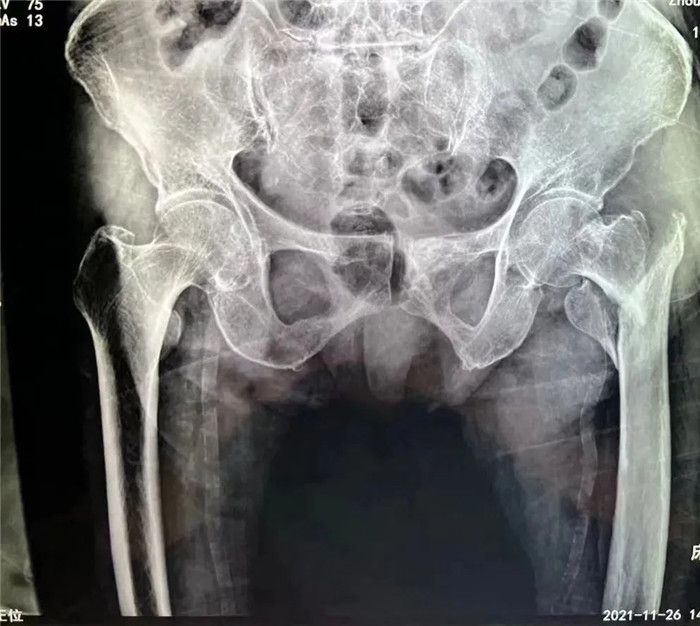

洪阿婆家住東港,前段時(shí)間在家行走時(shí)不慎摔倒,疼痛難忍,無法活動(dòng)。家人遂即送至我院,診斷為股骨粗隆粉碎性骨折。這是一種老年人常見的損傷,多是在摔倒時(shí)暴力導(dǎo)致股骨近端骨質(zhì)連續(xù)性斷裂,造成骨折。但是因老人年事已高,同時(shí)伴有腦梗死、肺部感染等多種并發(fā)癥,無論采取保守治療還是手術(shù)治療,都存在一定風(fēng)險(xiǎn),聽到這話的家屬異常沉重。

在手術(shù)團(tuán)隊(duì)及患者家屬的大力支持下,羅軍主任團(tuán)隊(duì)為洪阿婆實(shí)施了閉合復(fù)位INTERTAN內(nèi)固定術(shù)。雖然手術(shù)風(fēng)險(xiǎn)較大,但憑借精湛的技術(shù)及豐富的臨床經(jīng)驗(yàn),手術(shù)十分成功而且僅僅用了1個(gè)小時(shí),術(shù)中出血不多,術(shù)后患者恢復(fù)得很好,第二天就可以在起床活動(dòng),極大的提高了患者的生活質(zhì)量,避免了長(zhǎng)期臥床造成的并發(fā)癥。